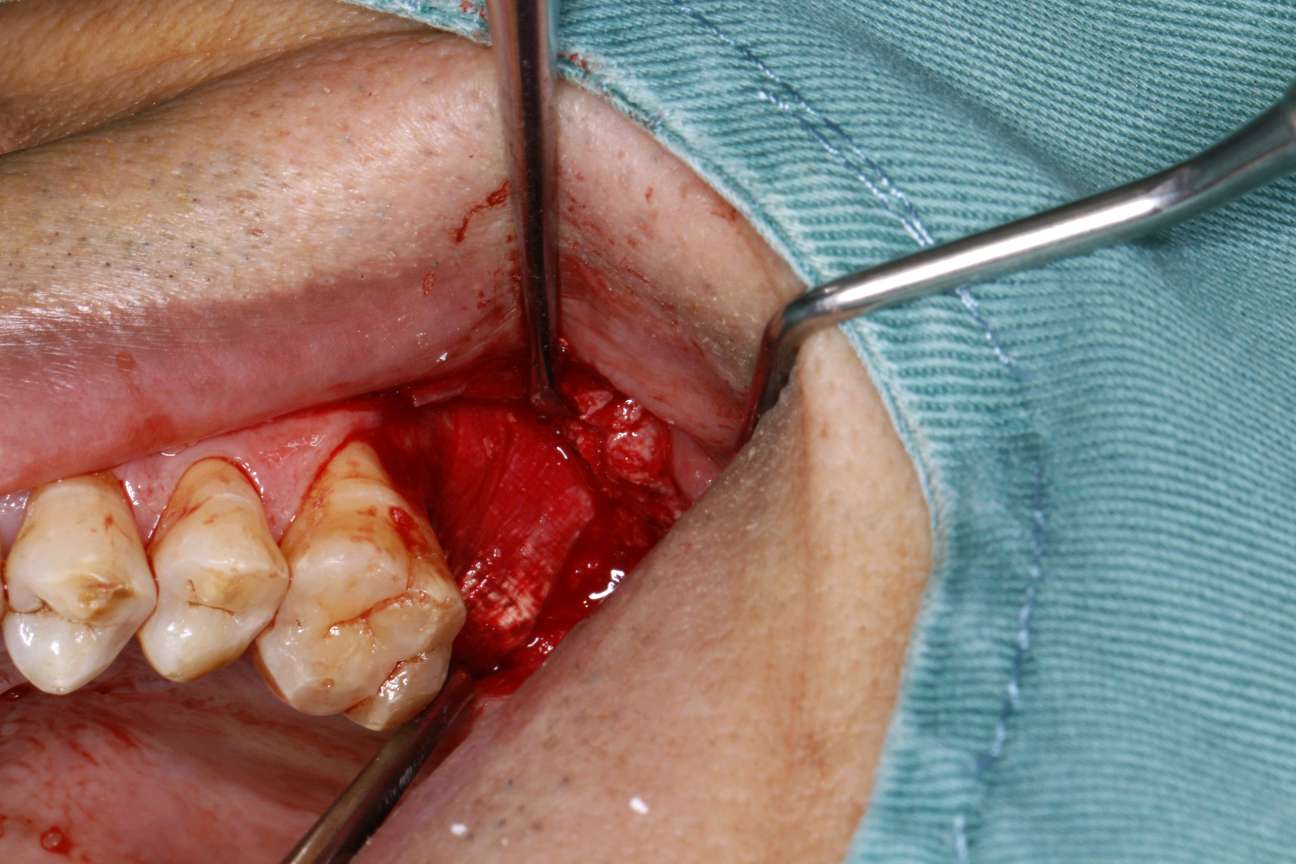

患者知情同意下,抽静脉血30ml,制作 CGF ,0.1%聚维酮碘溶液口内粘膜消毒,0.5%聚维酮碘溶液口外皮肤消毒,4%盐酸阿替卡因肾上腺素注射液2.0ml浸润麻醉,牙槽嵴顶切开粘骨膜,翻瓣。见腭侧大面积骨缺损,球钻定位,先锋钻导向,骨质钻扩大种植窝,行上颌窦内提,特殊冲顶器械敲击,抬高上颌窦底部骨质和黏膜。并攻丝植入 ITI 种植系种植体4.8*8mm,上封闭螺丝,腭侧骨缺损区植 bio - oss 骨粉0.25g及 CGF ,并盖 bio - Gide 膜及 CGF 膜,严密缝合,常规医嘱,15天拆线,抗生素自备。